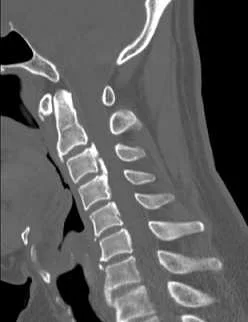

【111-2 醫學(六) 第74題】

18 歲女性,因急性下腹痛就醫,腹部腹部X光影像如圖,最可能的診斷為何?

這題的解題核心在於辨識腹部X光片中骨盆腔內不尋常的鈣化點,並結合年輕女性急性下腹痛的臨床情境,判斷最可能的診斷。